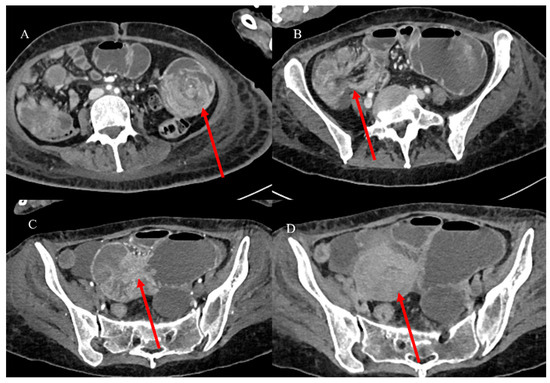

2.4. Small Bowel Tumors Causing Small Bowel Occlusion